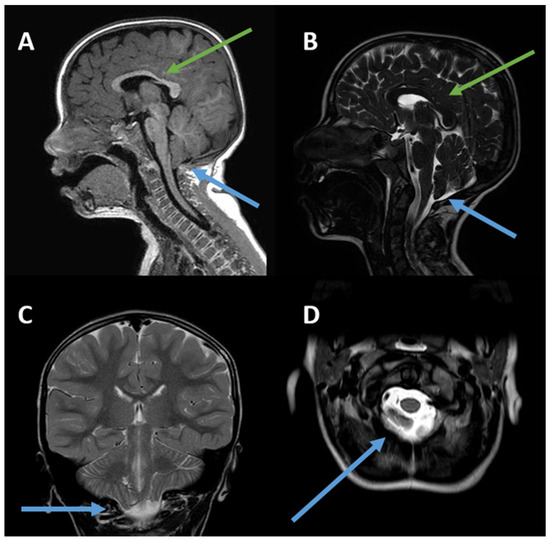

Background: TCF20-associated neurodevelopmental disorder (TCF20-NDD) is a heterogeneous clinical condition resulting from defects in gene-encoding Transcription Factor 20, which plays a key role in neuronal development and synaptic function. Here, we present a novel case involving an 11-year-old boy [...] Read more.

Background: TCF20-associated neurodevelopmental disorder (TCF20-NDD) is a heterogeneous clinical condition resulting from defects in gene-encoding Transcription Factor 20, which plays a key role in neuronal development and synaptic function. Here, we present a novel case involving an 11-year-old boy who was referred to us for a neuro-developmental disorder characterized by attention deficit hyperactivity disorder (ADHD), tremor in the upper limbs, tilted head posture, motor delay, impaired executive functioning, and oculomotor dyspraxia. Methods: Genetic tests were performed, including CGH array, molecular analysis of the FMR1 gene, molecular analysis using a next-generation sequencing gene panel targeted for spinocerebellar diseases, and finally, WES including mitochondrial genome analysis. A neuroimaging study of brain and spine was performed using MRI. Results: Trio Whole Exome Sequencing revealed a de novo pathogenic frameshift variant NM_001378418.1:c.5009dup, p.(Thr1671Aspfs*5) in the TCF20 gene. The MRI scan of the brain, cervical, dorsal, and lumbosacral spine revealed Chiari type I malformation. Regarding the pathogenic mechanism underlying Chiari I malformation, it could be found in the homology between TCF20 and the RAI1 gene, the latter being associated with alterations in the posterior cranial fossa. Conclusions: We emphasize the use of exome sequencing in patients with unclear clinical presentations, with awareness of TCF20-associated neurodevelopmental disorder; paying attention to brain MRI findings would be useful to further expand the phenotype of TCF20-NDD. Full article